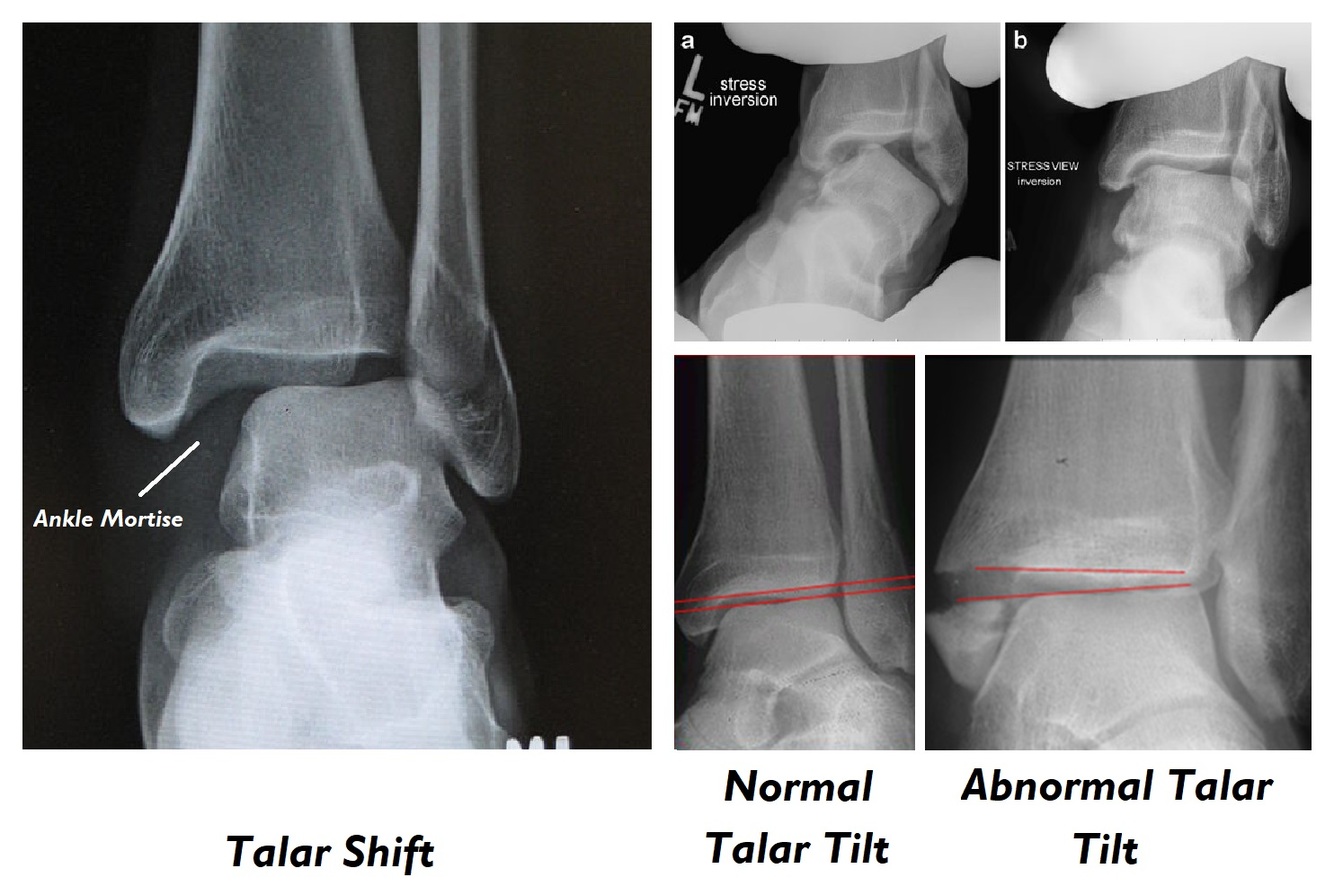

With talar shift, which way will the foot be rotated?

Inverted

By definition, the deltoid ligament must be ruptured if there is no medial malleolar fracture in which two conditions?

1. Talar shift occurring on a mortise AP view

2. Talar tilt with the talus and tibial plafond being non parallel

Talar shift poses a greatly increased risk of what?

Post traumatic OA

What treatment is required if talar shift is present?

Anatomical reduction and rigid internal fixation (ORIF)